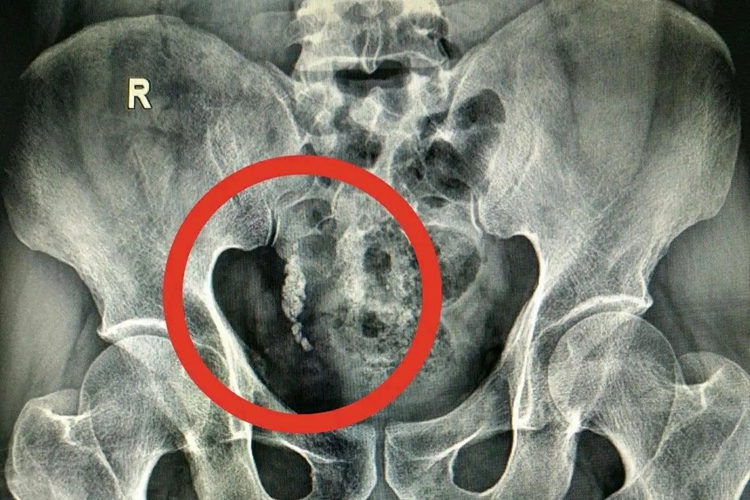

输尿管末端结石,常表现为疼痛、血尿,部分患者自觉结石排出。

输尿管末端结石的患者常自觉疼痛剧烈难忍、阵发性发作、疼痛位于腰部或上腹部,末端结石可沿输尿管走行,放射至同侧腹股沟,还可累及同侧睾丸、龟头,或者阴唇,患者可见镜下血尿;输尿管结石引起尿路完全性梗阻时,可出现恶心、呕吐;结石伴感染可有尿频、尿急、尿痛,部分患者可自觉结石排出。查体可见腹部平软,无明显压痛及反跳痛,但肾区叩击痛明显。